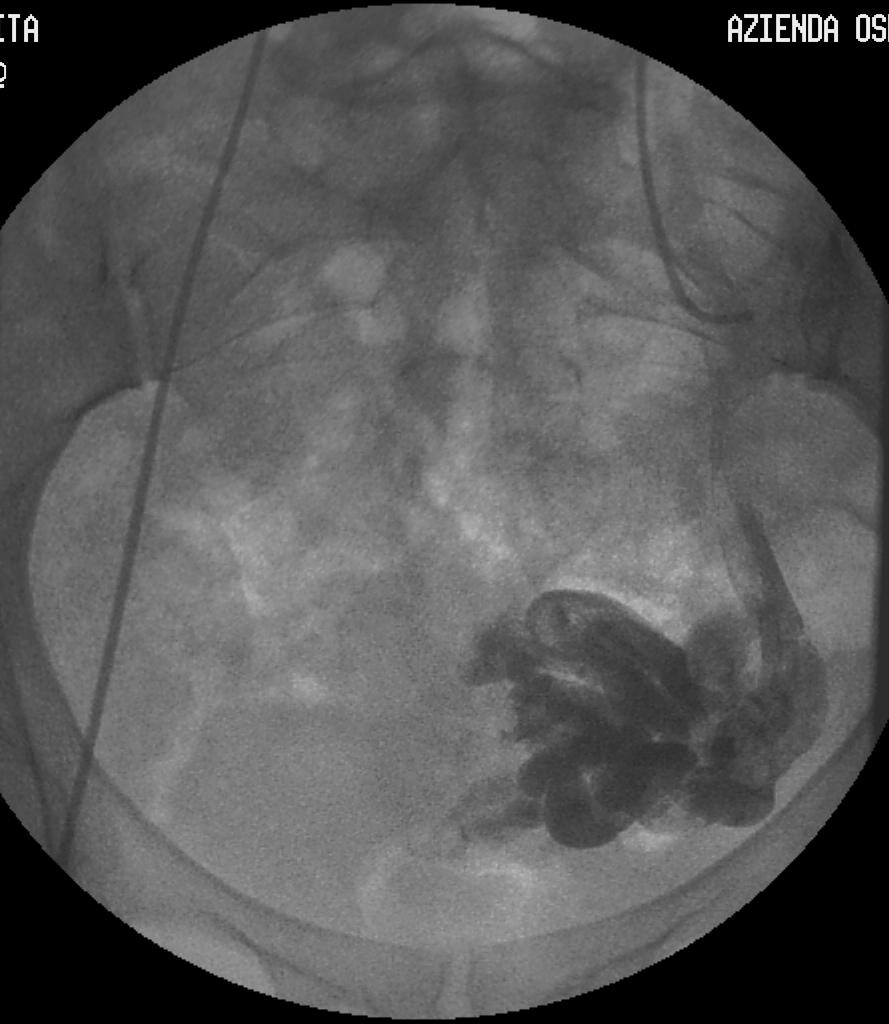

栓塞左右卵巢曲张的静脉后,下面的重点是髂内静脉。有些病人在卵巢静脉栓塞后仍然持续慢性盆腔疼痛,可能由于不常见的侧支循环,栓塞髂内静脉可能有帮助。为了在硬化栓塞治疗髂内静脉曲张时让其完全阻塞,需要使用内径较大的闭塞球囊导管(也许需要直径11.5mm的导管)。向在栓塞卵巢曲张静脉一样,也使用明胶海绵和5%鱼肝油酸钠的混合泥浆。需用明胶海绵/鱼肝油酸钠泥浆的量,仍然用注入使曲张的髂内静脉丛充盈的造影剂的量来估算。同样,要让实际注入栓塞剂(泥浆或者“布丁”)的量比估算量稍小。球囊需要保持扩张大约10分钟以减小盆腔回流静脉血流的稀释作用。髂内静脉支流中很少使用弹簧圈,因为有脱落造成肺循环栓塞的风险。